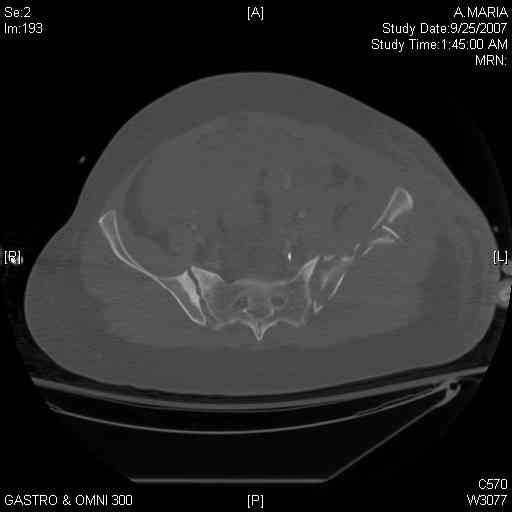

[Ortho] comminuted crescent fx

40 ish female ejected from car. Unstable, DPL negative, went to angio and had her pelvic bleeds embolized after many units of blood. GCS 6, floating elbow, clavicle, bothbones, etc.

My standard approach to  this pelvis would be posterior, reduce/lag/plate  thecrest, reduce/plate the caudal extent on the posterior crest and 1-2 lags back to front. In this case, the crest comminution seems to make plating all

the way to the ASIS useless, as the plate would be on free floating fragments. Would plating the posterior extent of the fracture to secure the

reduction at the SI joint and 2 screws back to front be sufficient fixation? Would anyone do a perc reduction and perc back to front screws, and would that be sufficient if the SI joint could be reduced (although I don't see how this could be accurately reduced closed). Would an ilioninguinal with a pelvic brim plate and posterior column screws be a better approach, although reducing the SI would be more indirect and less accurate?